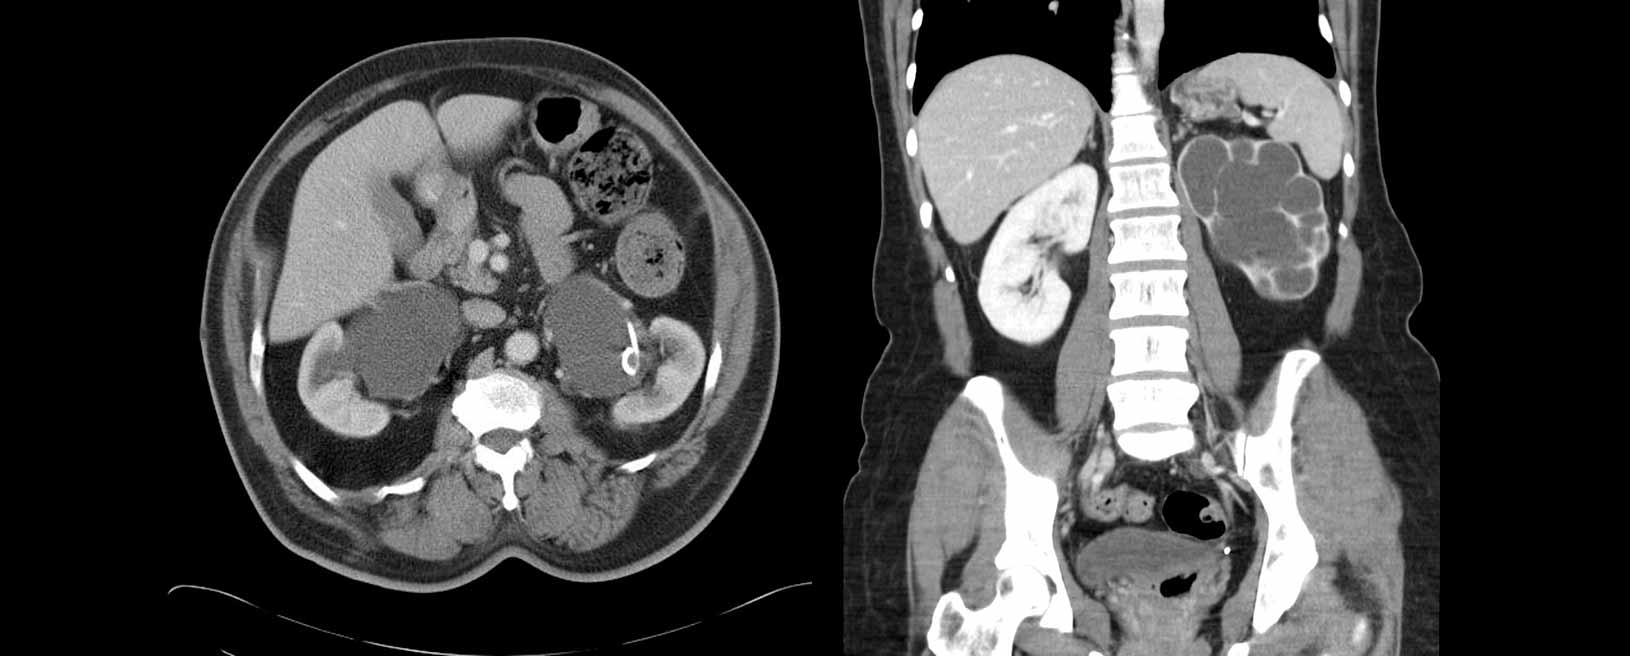

Son múltiples las causas de la enfermedad renal crónica; sin embargo, entre las más importantes se encuentra la diabetes mellitus (25%), la la enfermedad vascular (16%), glomerulonefritis (13%), nefritis intersticial (8.3%), enfermedad poliquística del adulto (6.9%) o uropatía obstructiva. De igual manera, si la lesión renal aguda no se corrige a tiempo, esta progresa a enfermedad renal crónica.